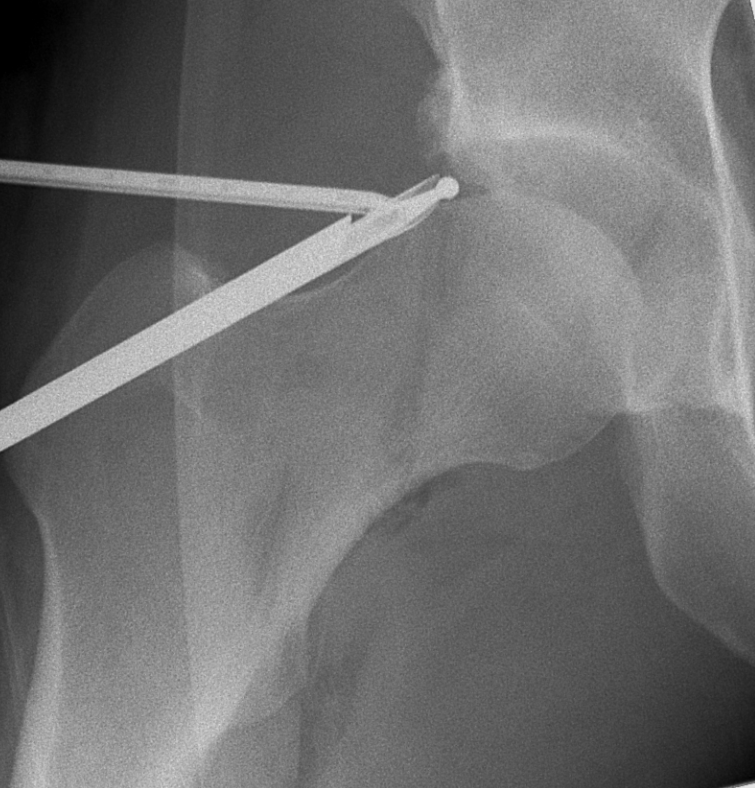

Intraoperative x-ray taken during a hip arthroscopy removing a pincer lesion of the acetabular rim

Femoroacetabular impingement (FAI) – extra bone around the hip that causes painful pinching or restricted motion. This can either be extra bone on the pelvis side (pincer lesion) or femur side (cam lesion)